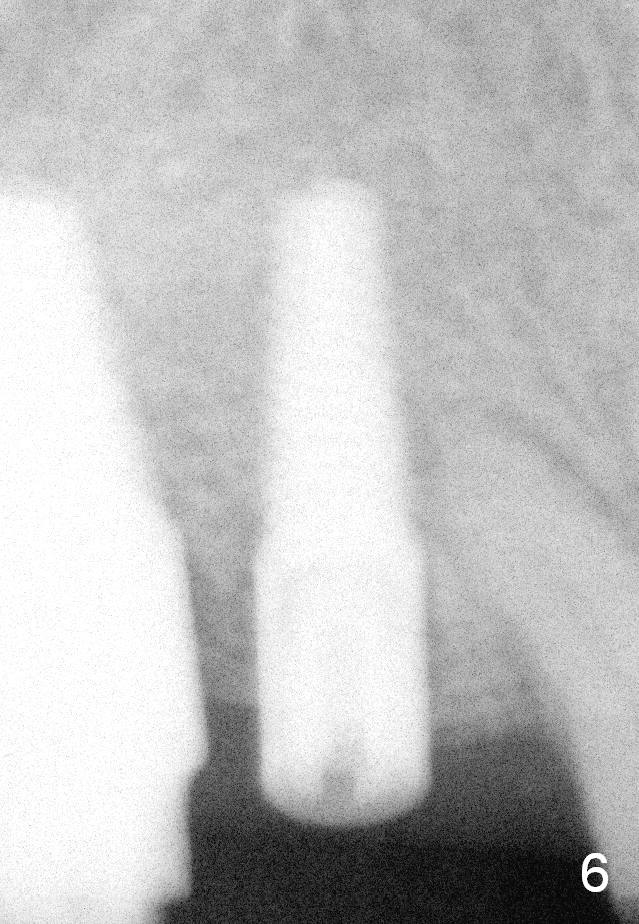

Eight months postop (Fig.6), he returns for final restorations (Fig.7 (buccal), 8 (lingual view)). There is no bone loss nearly 2 years post cementation (Fig.9).